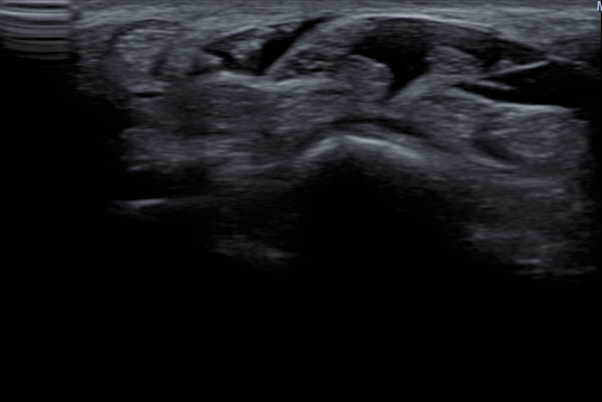

그래서 바로 초음파 검사와 X-ray를 시행했어요.

거기에 목디스크 감별진단까지!

그림2.png

결과는?

목디스크였습니다

콕병원에서는 이런 이유로 초음파 검사를 적극 활용하고 있어요.

X-ray로는 보이지 않는 인대, 관절, 근육의 상태를

실시간으로 확인할 수 있거든요.